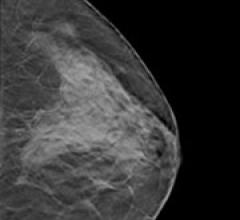

Despite decades of progress in breast imaging, one challenge continues to test even the most skilled radiologists ...

September 26, 2011 — Hoag Breast Care Center recently became the first breast care center in California and one of a handful in the United States offering 3-D digital breast tomosynthesis for breast cancer screenings. The technology promises to improve breast cancer detection, especially in young women and women with radiographically dense breast tissue.